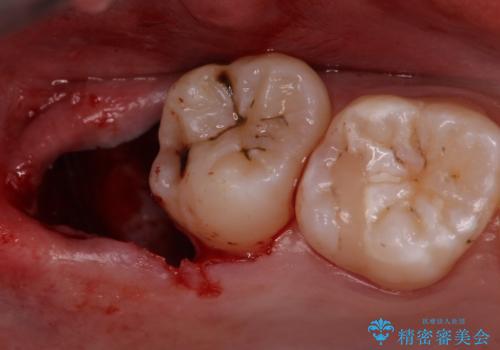

- 親知らず抜歯をご希望で来院されましたが、手前の歯が歯ぐきに覆われていたため抜歯と同時に歯ぐきの除去を行います。

そのような時は周りの歯茎を除去することで歯の高さを出すことができる場合があります。

今回は親知らずの抜歯と同時に周りの歯茎の除去を行いました。